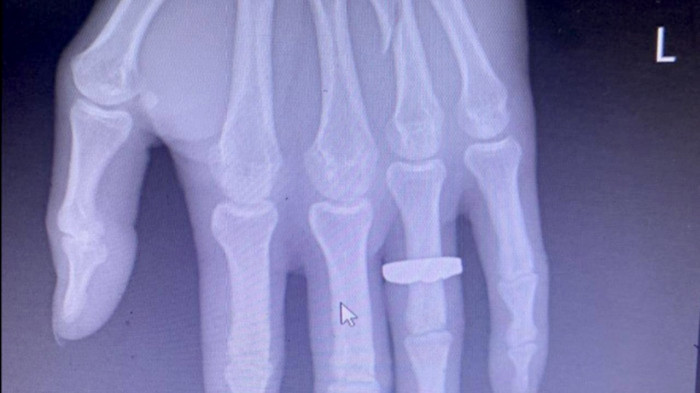

Sau đó, anh Sáng được người dân giúp đỡ sơ cứu, gọi xe ôm ra khu vực bắt xe về Quảng Ninh. Khoảng 22h ngày 30/10, về đến Quảng Ninh, anh Sáng vào Bệnh viện Đa khoa Bãi Cháy điều trị trong tình trạng bị gãy xương áp út bên tay trái, đa chấn thương đầu, mặt…

Hình ảnh xương ngón tay áp út bàn tay trái của anh Sáng bị đánh gãy